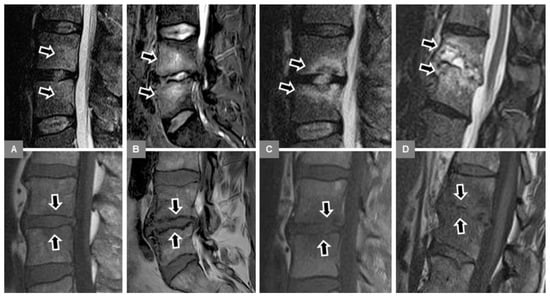

3.6. Modic Type 2 and 3 Endplate Changes